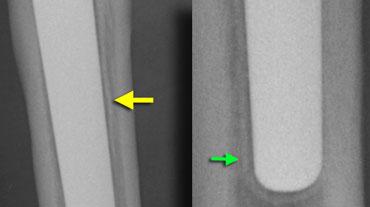

Vùng thấu quang mỏng dọc theo ranh giới xương-kim loại do mô xơ là hiện tượng thường gặp (80%).

Chúng phải nhỏ hơn 2mm và đi kèm với một đường xơ cứng song song với nó.

Nếu chúng ổn định trong 2 năm thì sự cố định bởi mô xơ chắc đã xảy ra.

Che chắn ứng suất hay tiêu xương được thấy ở những vùng tương đối không chịu lực.

Các lực được truyền qua thân xương đùi tương đối cứng và biểu hiện là loãng xương ở vùng xương đùi gần với mỏng vỏ xương và tiêu xương cổ xương đùi.

Điều này được thấy ở phía trong là tiêu xương calcar, do calcar đã mất chức năng của nó (hình).

Nó còn được gọi là làm tròn calcar.